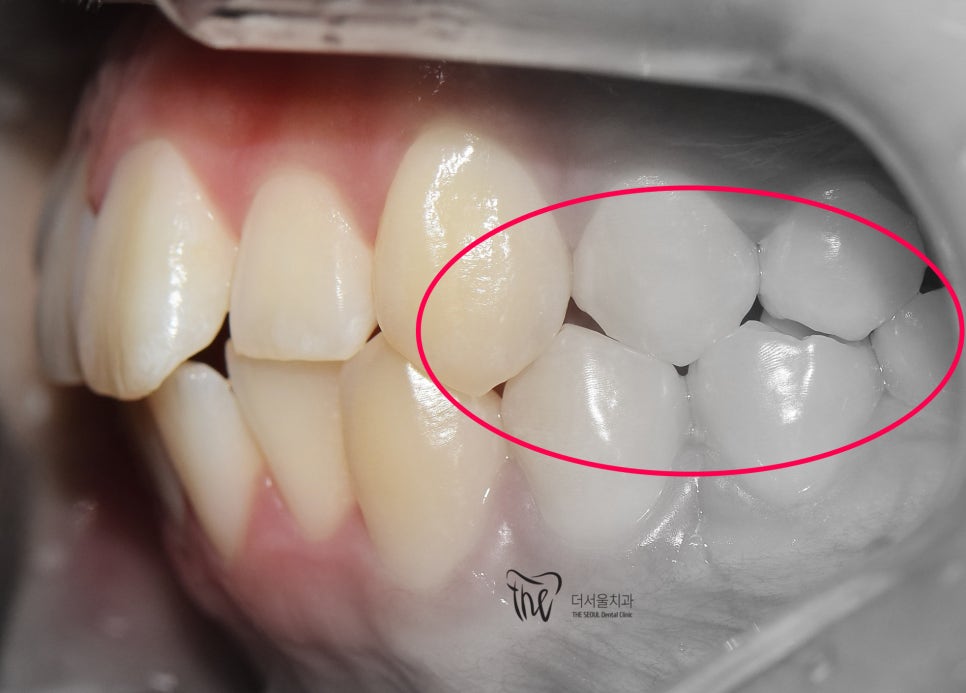

그러나, 좌측에서 바라봤을 때는 어금니들이

부정교합을 띄고 있는 것을 볼 수 있습니다.

즉, 거꾸로 물리는 반대교합의 양상을 보여주고

있고 이런 증세 때문에 턱관절의 통증까지도

조금씩, 치열이 가지런해지는 것을 볼 수 있으며

이미 여기 시점으로부터 어금니들이 서로

거꾸로 물리는 반대교합의 양상은 사라졌습니다.

치열이 고르게 바뀐거 뿐만이 아니라

앞니들이 많이 앞쪽으로 뻐드러졌던

모습의 변화를 함께 볼 수 있으며

처음에 오셨을 때와는 다르게,

구강 내 어금니들이 위, 아래로 서로 다

고르게 다 맞물릴 수 있도록 바뀐 모습 또한

한번에 보실 수 있습니다.